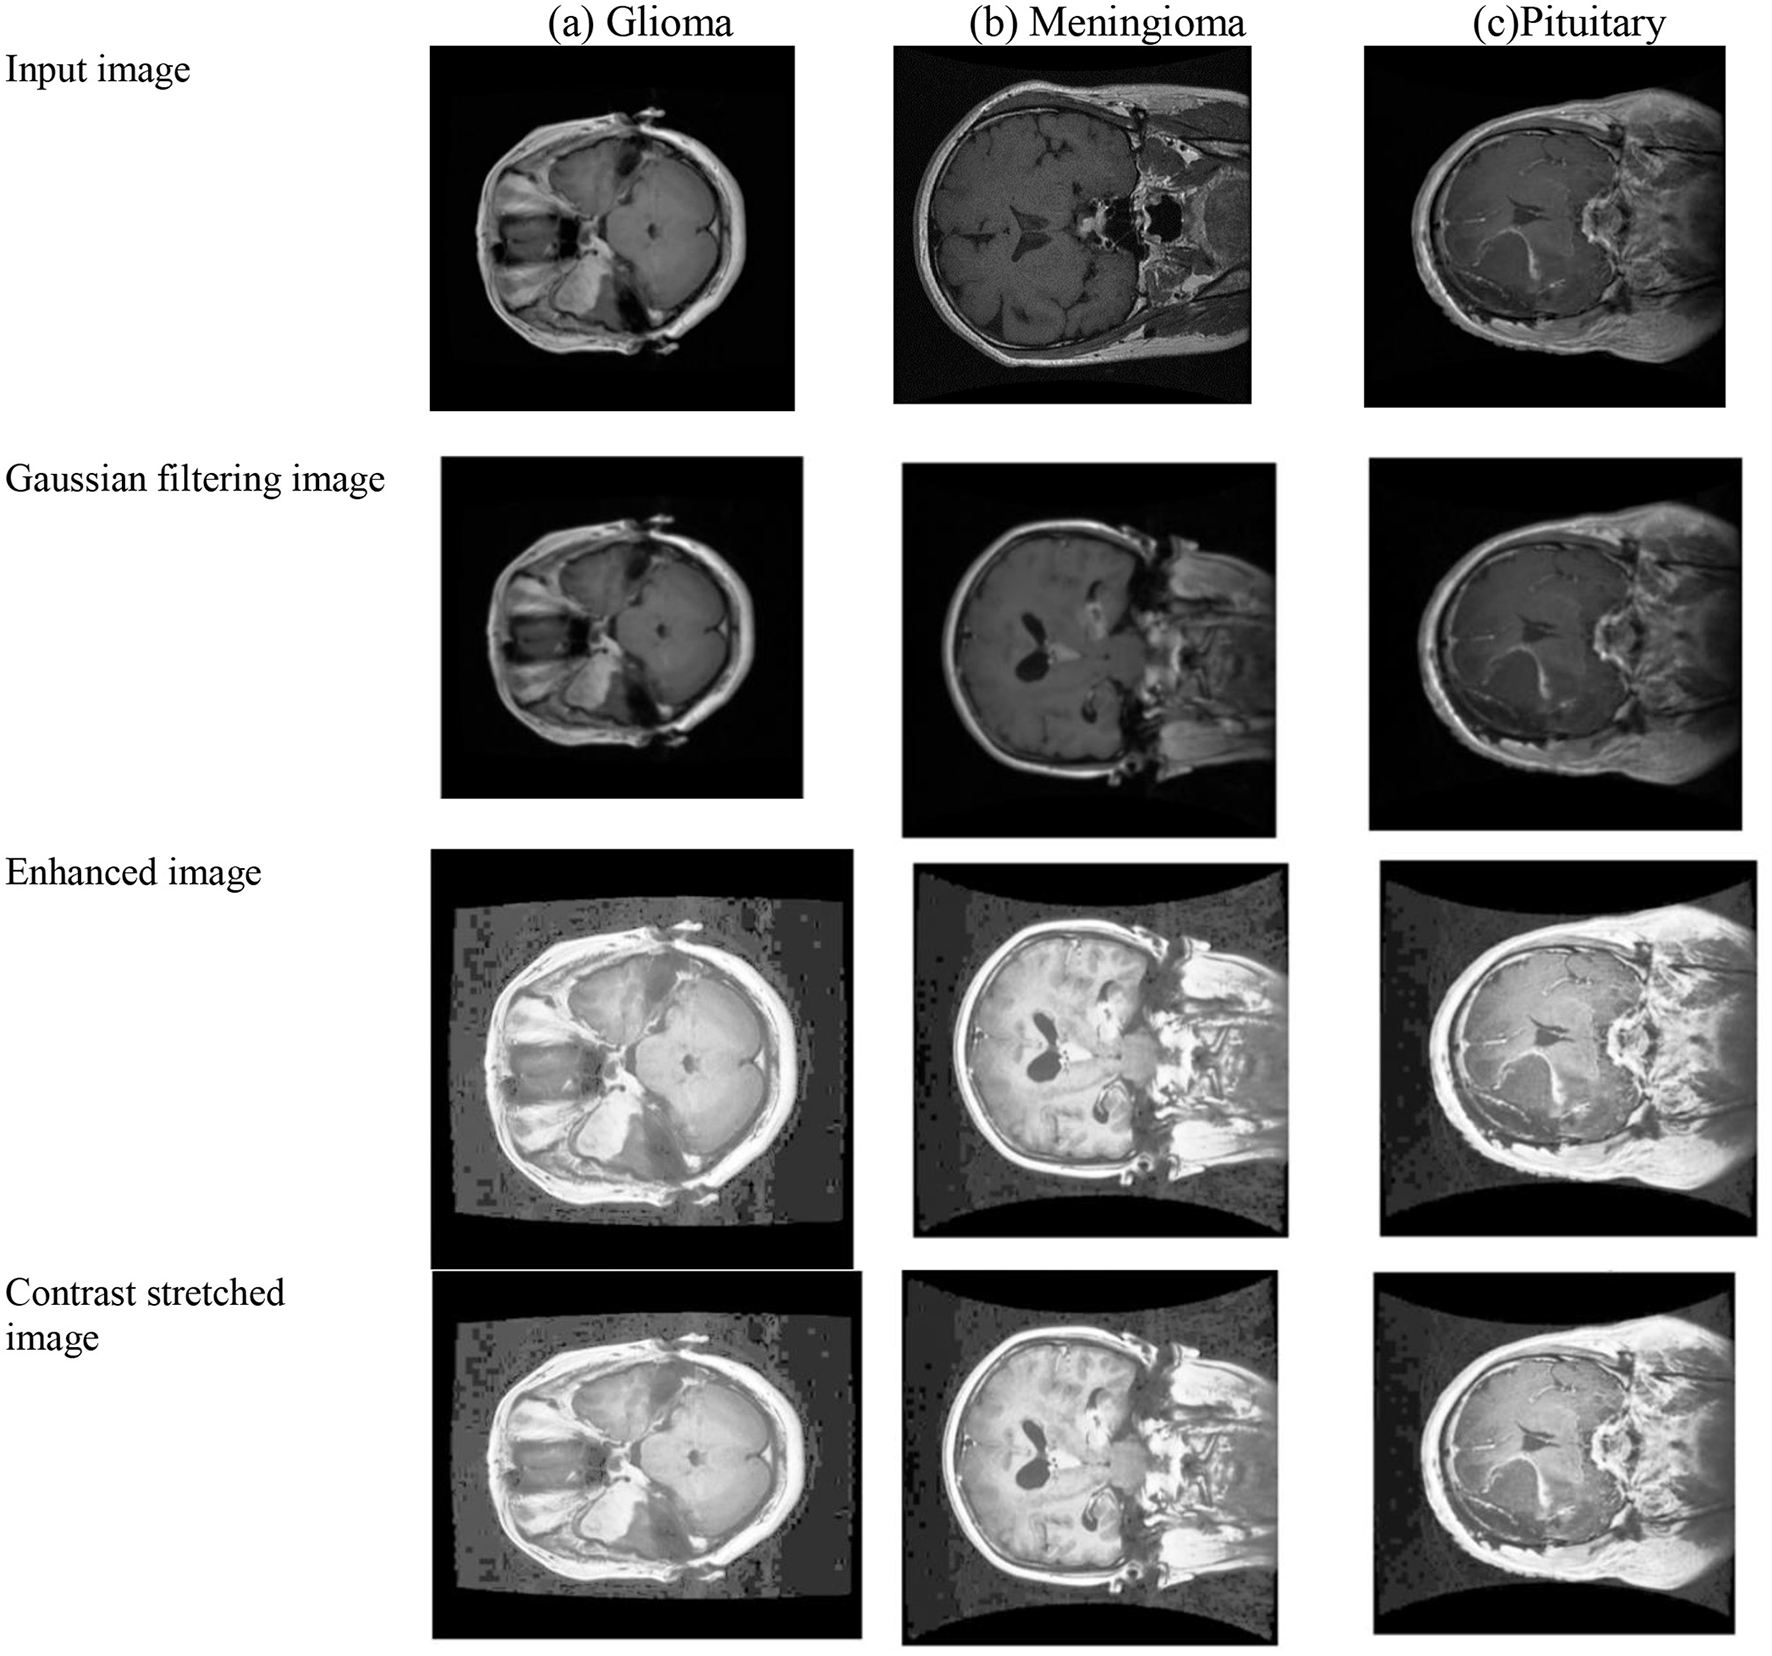

In the depicted Figure 4, a comprehensive representation of the pre-processing stages is showcased through a sequence of Figures 4a–c, each corresponding to a distinct BT case. The initial input Image reflects the raw state of the medical images before any processing. The subsequent Gaussian filtered image demonstrates the efficacy of Gaussian filtering, a step crucial for noise reduction and the elimination of unwanted variations in the images. Following this, the enhanced image illustrates the outcomes of histogram equalization and contrast stretching, emphasizing the improved visual quality and clarity of critical features. The final contrast stretched output image presents the refined result after contrast stretching, further enhancing image contrast for effective feature extraction. This progression highlights the success of the proposed pre-processing steps in preparing the BT images for advanced analysis, including feature extraction using PVT and TDA.